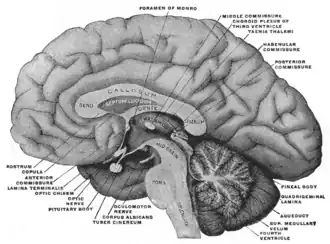

Medial aspect of a brain sectioned in the median sagittal plane. (Subfornical organ not labeled, but fornix and foramen of Monro are both labeled near the center.) | |